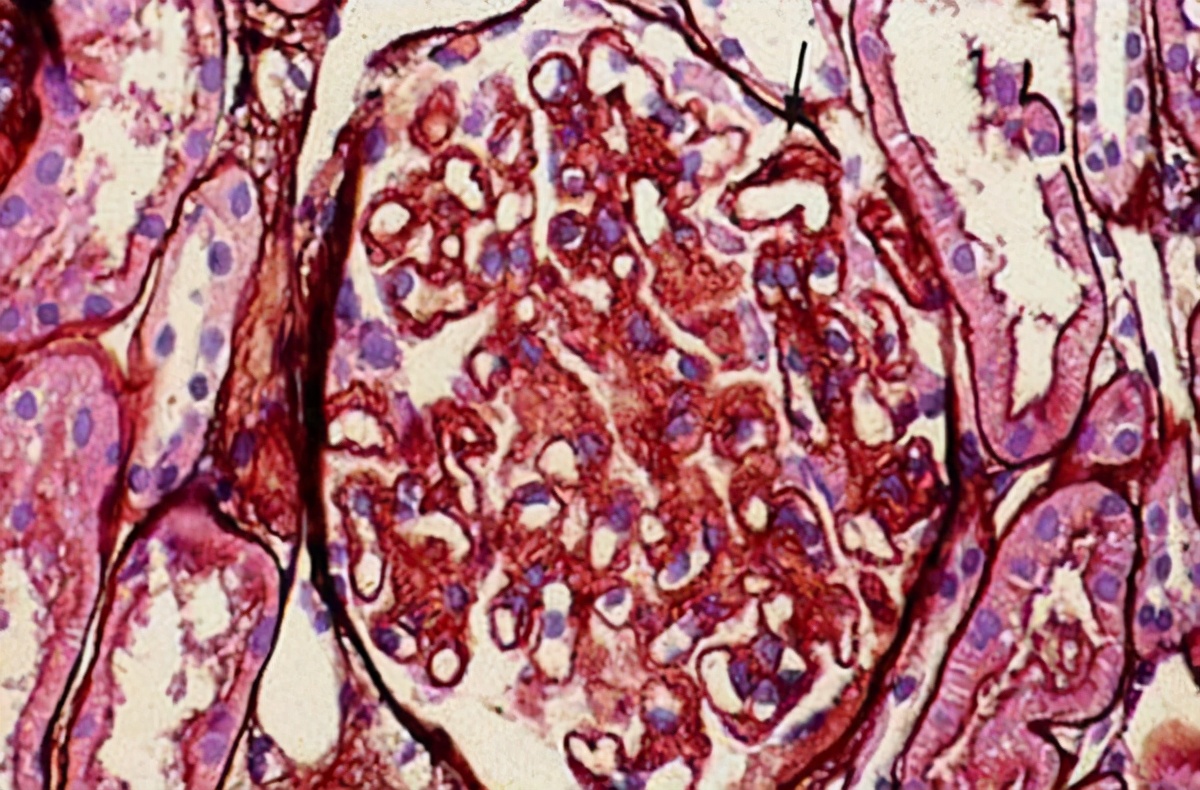

肾病综合征(NS)是一种比较常见的肾脏疾病,在老年人群体多发,可由多种病因引起。是以肾小球基膜通透性增加,表现为大量蛋白尿、低蛋白血症、高度水肿、高脂血症的一组临床症候群。在治疗上存在一定难度,治愈可能性比较小。在发病初期,病症比较轻微时,一般采用药物治疗,控制疾病,防止进展恶化。

1、病理类型。一般微小病变型肾病和轻度系膜增生性肾小球肾炎的愈后较好,微小病变性肾病部分患者可自发缓解,治疗缓解率高,但缓解后易复发。早期膜性肾病有较高的治疗缓解率,晚期虽难以达到治疗缓解,但病情多数进展缓慢,发生肾衰竭较晚。

系膜毛细血管性肾小球肾炎以及重度系膜增生性肾炎,疗效不佳,愈后较差,较快进入慢性肾衰竭。对局灶节段性肾小球硬化,影响愈后的最主要因素是尿蛋白的程度和对症治疗的反应。自然病程中,无肾病综合征表现者10年存活率为90%,而表现为肾病综合征的患者,10年肾脏存活率为50%。